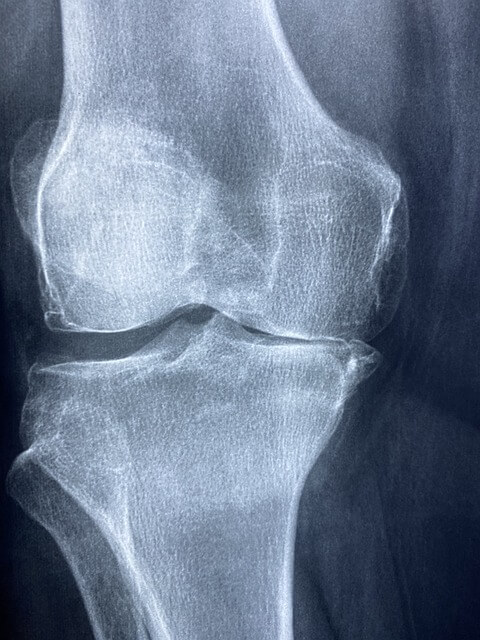

무릎 관절염으로 인한 심한 통증과 변형이 있는 경우, 근위경골절골술이 적합할 수 있습니다. 병원에 가면 의사는 검사, X-ray 및 MRI를 통해 뼈의 상태를 평가하고 수술이 적합한지 여부를 결정하게 됩니다.

근위경골절골술 후 회복 과정